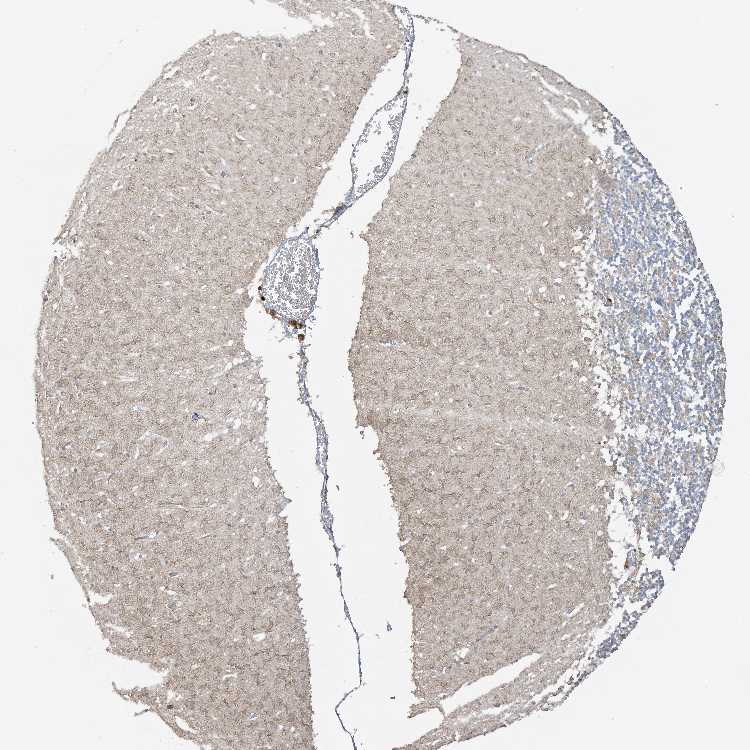

CEREBELLUM - Antibody stainingi

Antibody staining in the annotated cell types in the current human tissue is reported as not detected, low, medium, or high, based on conventional immunohistochemistry profiling in selected tissues. This score is based on the combination of the staining intensity and fraction of stained cells.

Each image is clickable and will lead to virtual microscopy that enables deeper exploration of all samples and also displays staining intensity scores, fraction scores and subcellular localization as well as patient and tissue information for each sample.

Antibody HPA031415Antibody HPA031417

Purkinje cells MediumMedium

Cells in granular layer LowMedium

Cells in molecular layer Not detectedNot detected